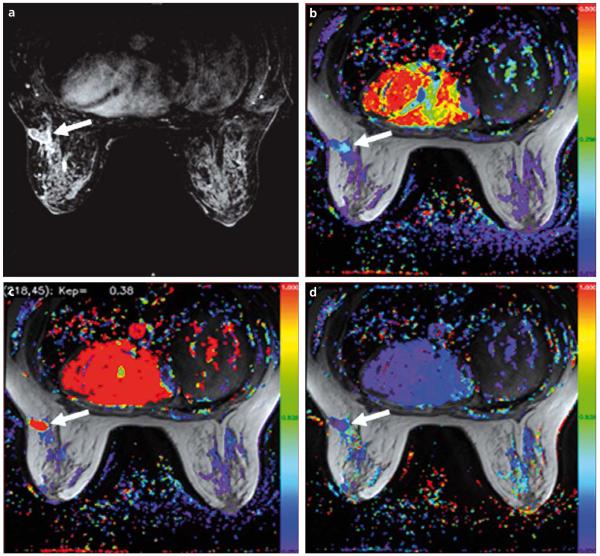

Figure 5.

a–d. A 43-year-old female with breast cancer. Axial T1W DCE-MR image demonstrates an enhancing lesion in the left breast (arrow) (a). Color-coded Ktrans (b), Kep (c) and Ve (d) maps delineate the tumor (arrows).